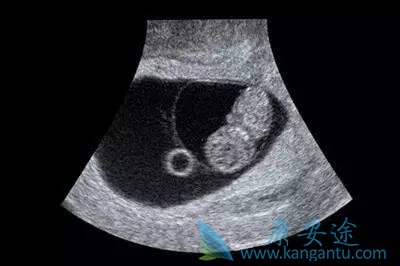

第一次B超检查—孕6-8周

这个时期的超声检查主要目的是确定是否妊娠,医生会观察妊娠囊的大小、有无胚芽及胎心搏动,从而判断是否怀孕,并核对孕周,排除宫外孕及胚胎停止发育等意外情况。对于移植了两枚胚胎的准妈妈,这个时期通过观察妊娠囊数目可以明确是单胎还是双胎,以及初步判断两个胎儿之间的位置关系。